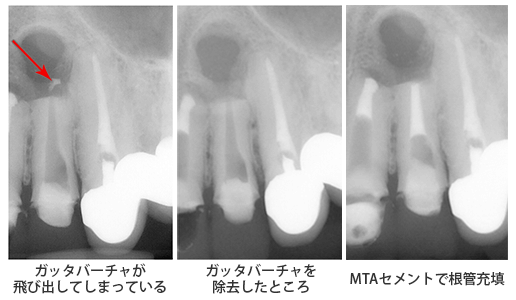

今回は前回の続きで、根の外に飛び出てしまったガッタパーチャをOKマイクロエキスカを用いることによって、除去することが出来た症例をお見せします。

前回のように根の中から外に飛び出していても、繋がっていればまだ少しは除去しやすいのですが、(そうは言ってもなかなか難しいです)繋がっていなくて完全に飛び出てしまった状態は非常に難しいです。

レントゲンでみると簡単そうに見えますが、実際はマイクロスコープで根の中を覗き、根の外まで見ないといけないのです。根の外に向かって空いてる穴の大きさはおよそ直径1ミリです。

どうですか?見事に除去できましたね。